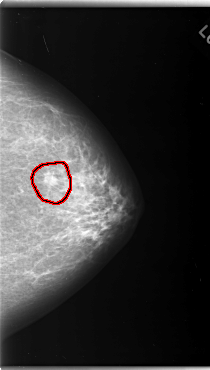

C_0124_1.LEFT_MLO

FILE: C_0124_1.LEFT_MLO.OVERLAY

TOTAL_ABNORMALITIES 1

ABNORMALITY 1

LESION_TYPE MASS SHAPE OVAL MARGINS MICROLOBULATED

ASSESSMENT 4

SUBTLETY 5

PATHOLOGY MALIGNANT

TOTAL_OUTLINES 1

BOUNDARY